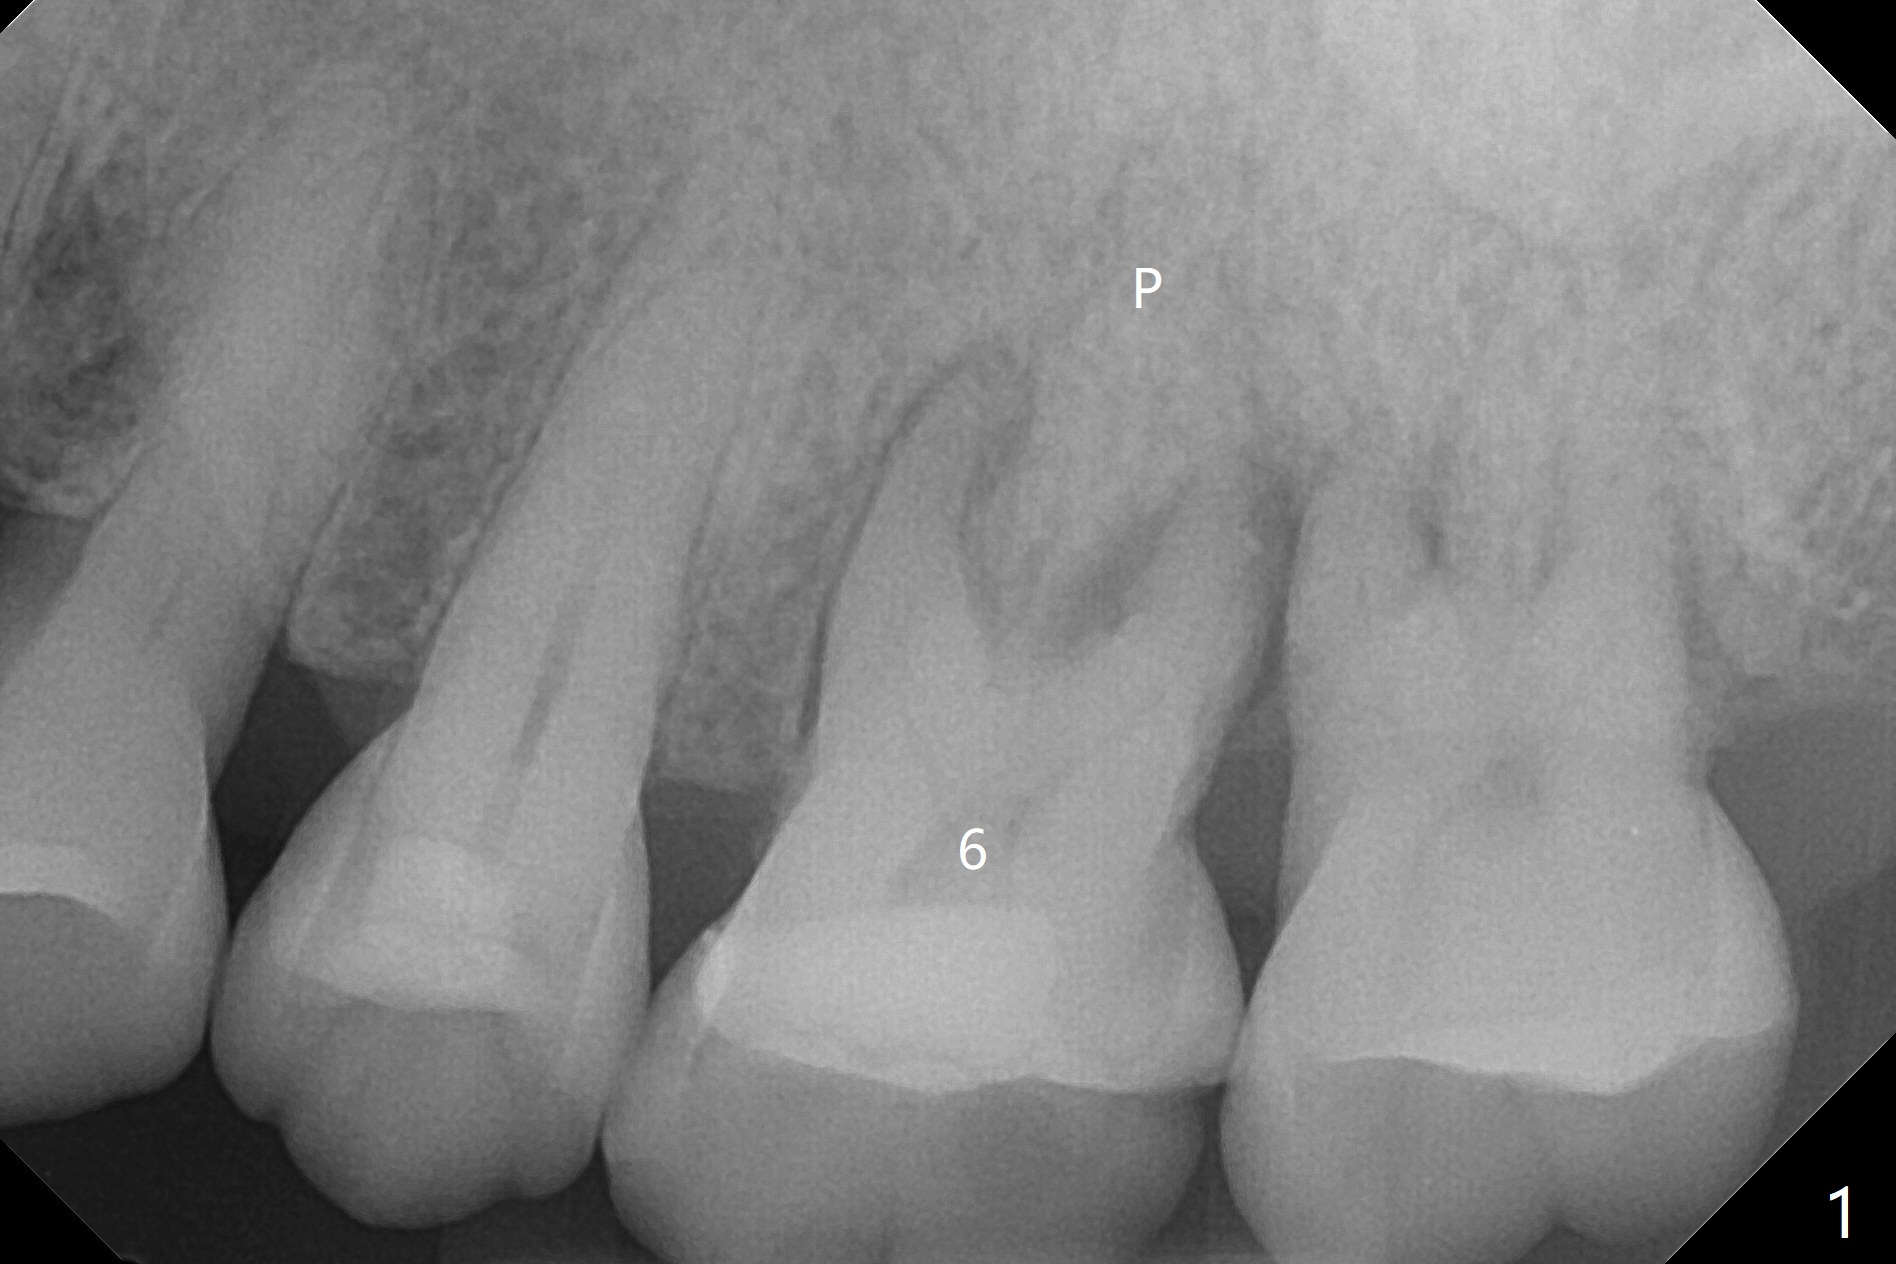

64岁男左上6疼痛(图一),可能继发于牙周病-牙髓炎综合征以及咬合创伤(右上2缺失),深洗,咬合调整后无效,要求拔除,经过解释,同意植骨,颊侧,腭侧骨板均有破坏,中隔正常,放置粘性骨粉后(图二),覆盖PRF膜(图三:>)和GEM Cap (C,9-12个月可吸收膜,Curves when hydrated to facilitate placement),牙周胶水固定(节省时间)。最后牙周敷料(进入左上3残根间隙)。术后两个星期牙周敷料脱落,一个月颊侧骨板开始塌陷(图四:箭头)。